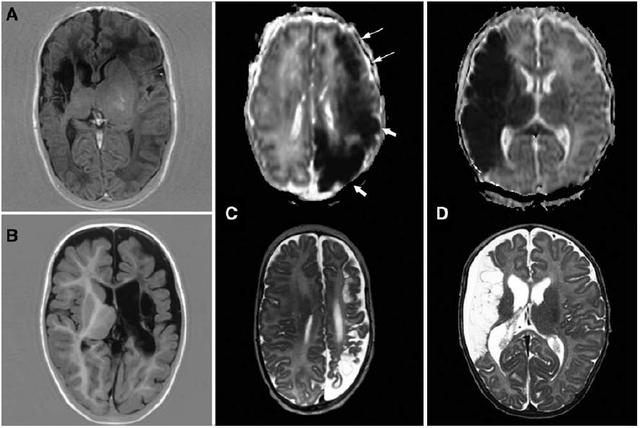

研究者在3例早产儿中观察到皮层灰质完全不受累,以及皮层下白质空腔形成(见图示);在其他4例晚期早产儿中观察到皮层灰质部分不受累。而在足月儿中,只有1例患者出现了皮层灰质部分不受累,其他患儿均有皮层灰质受累。

图为4例大脑中动脉(MCA)卒中的患儿磁共振(MRI)表现为不同程度的皮层受累的情况。有2例患儿表现为皮层灰质完全不受累,A和B分别为32周和28周早产儿在3个月和18个月时的影像学表现;C图为35w+3的1例患者的ADC图像,显示大脑中动脉和大脑后动脉卒中。尽管ADC成像显示枕叶和顶叶皮层灰质和白质均有受累(粗箭头所示),但额叶的皮层灰质没有受累(细箭头所示)。医|学教育网整理这种部分受累的形式在3个月时仍然保留,即枕叶几乎完全损伤,但额叶皮层部分保留。该例患儿后来出现难治性癫痫并需要半球切除术治疗;D图为一例足月MCA卒中的患儿,皮层灰质和皮层下白质均有受累。3个月MRI显示既往卒中区域内灰质完全破坏